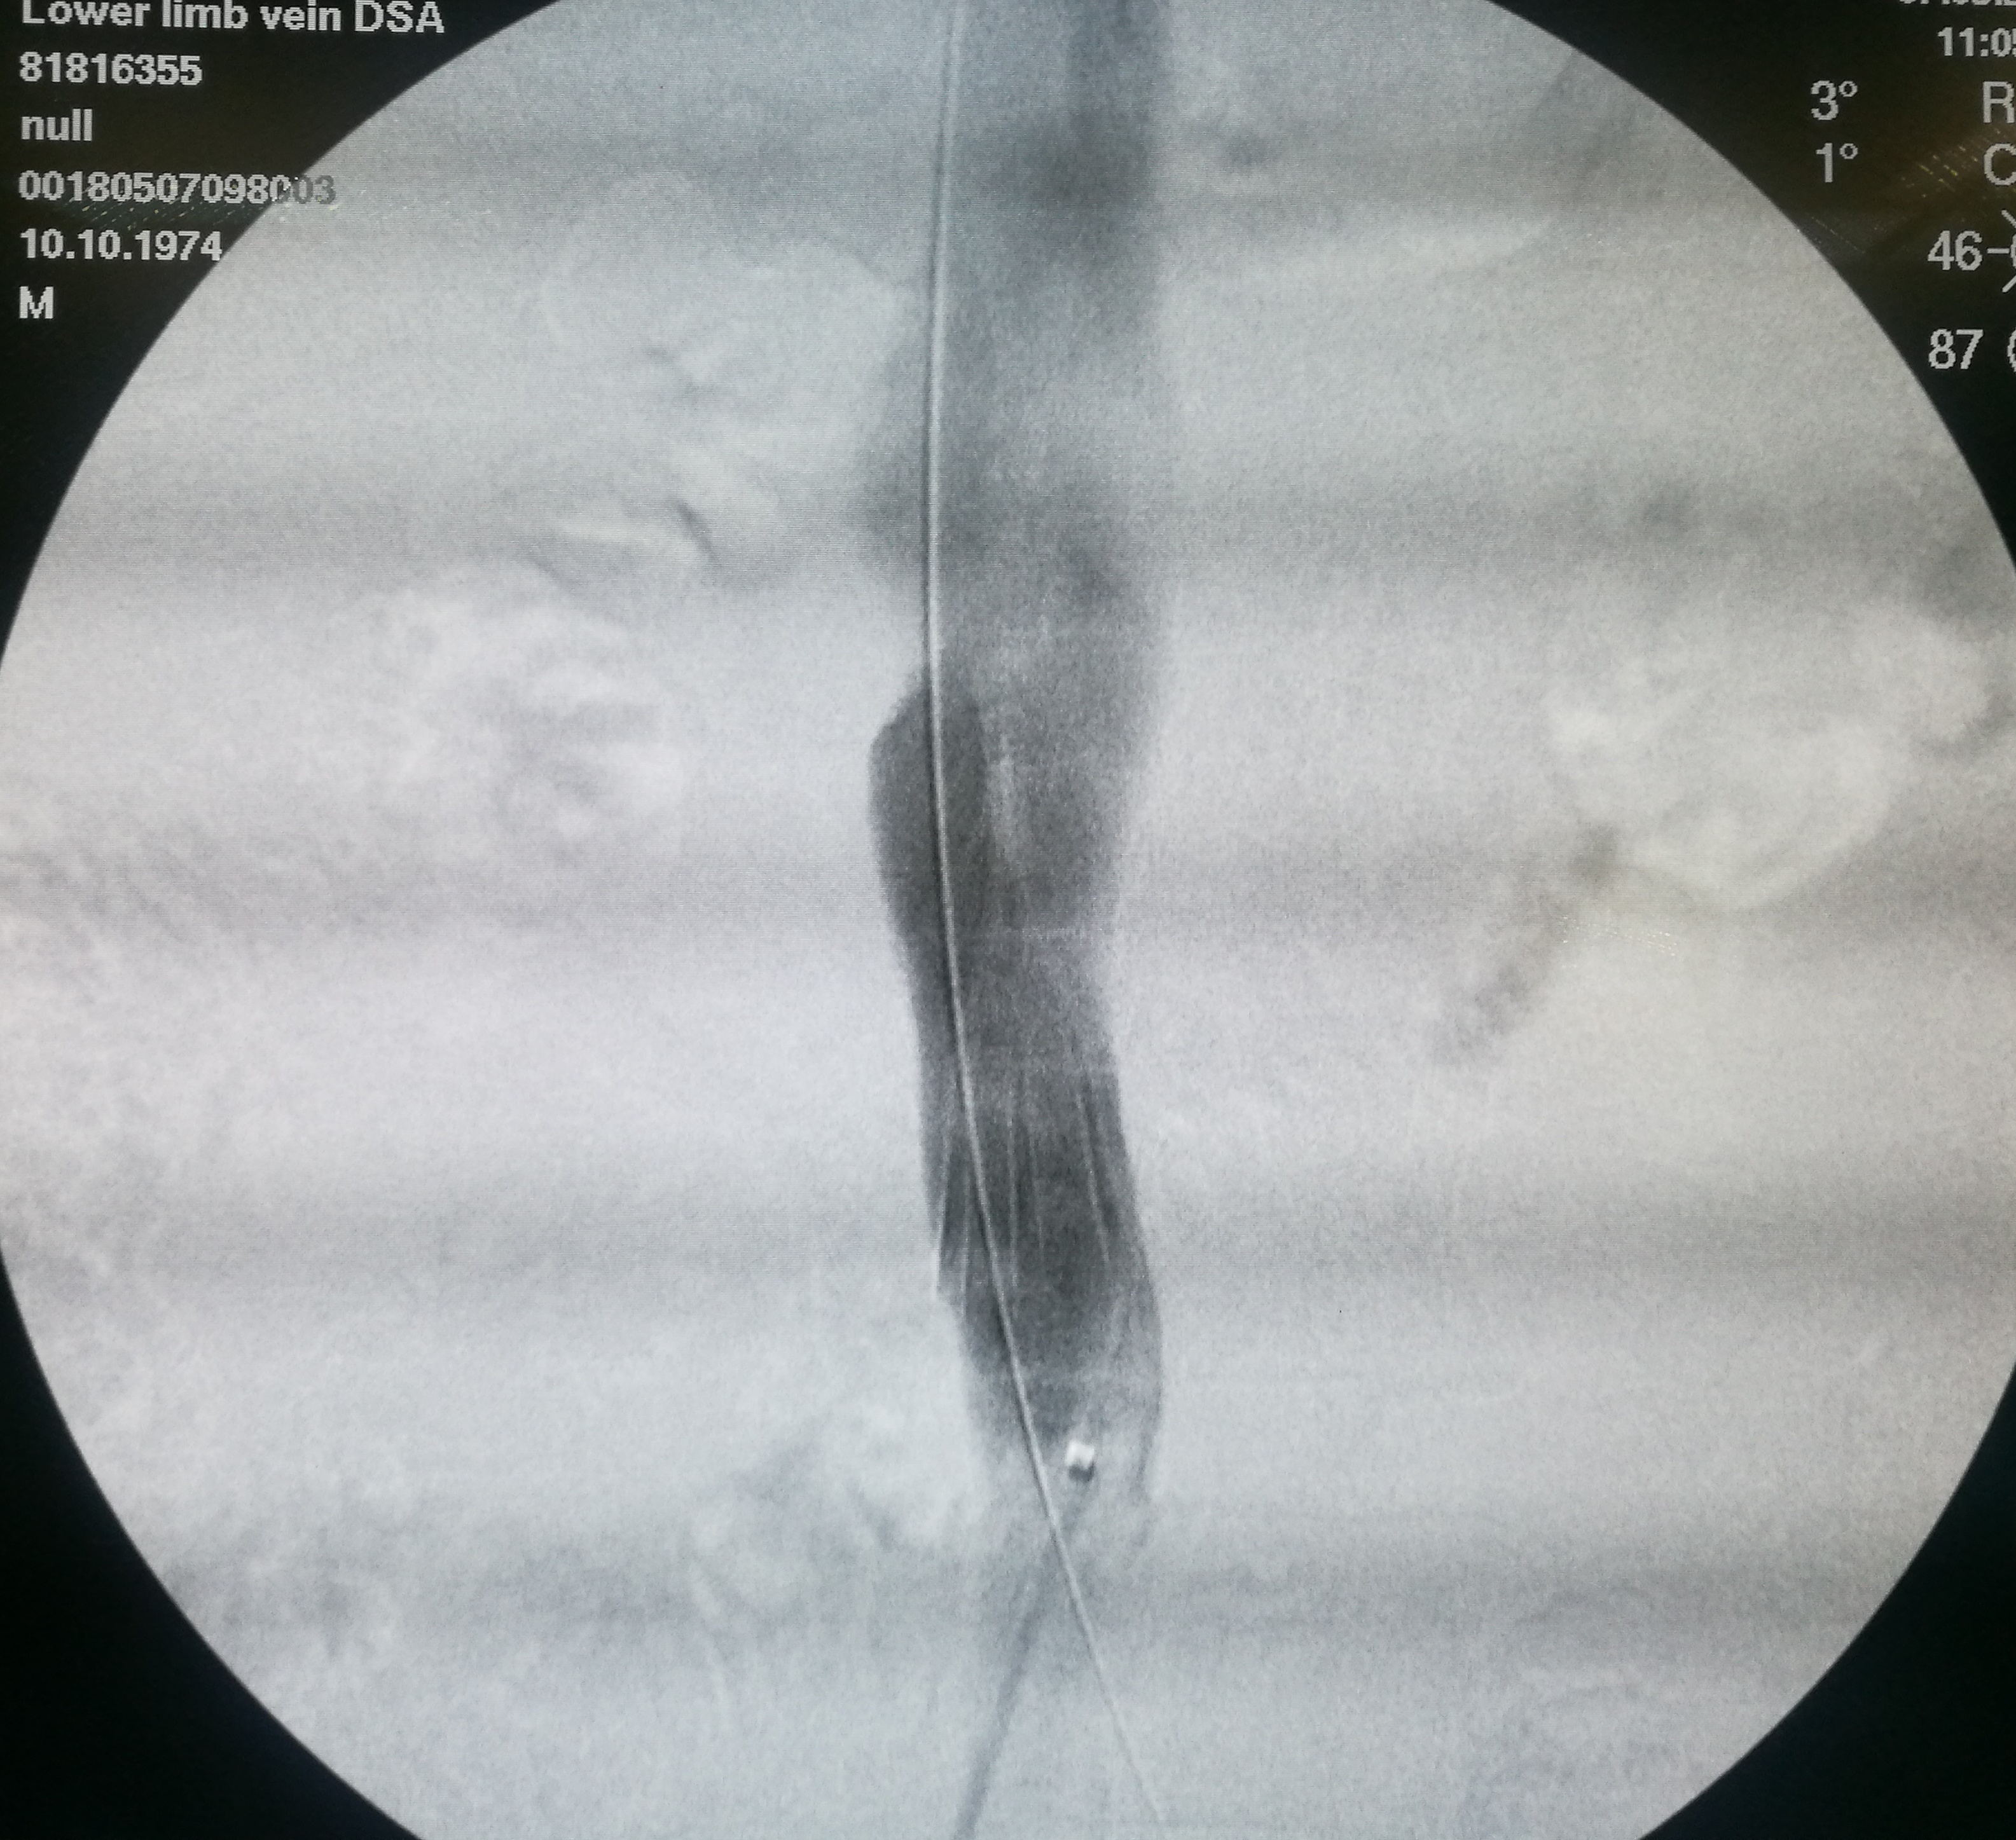

第三个患者是昨天做的,也是反复左下肢深静脉血栓,最近又发作。本次在超声引导下使用肝穿针穿刺左股静脉(其内充满血栓,盲穿无回血),配合超滑导丝,艰难前行约7-8cm后送入血管鞘,之后用导管导丝配合,进入到中线右侧,但从导丝头端的活动度看,未能回到下腔静脉。穿刺右侧股静脉,用SIM1导管从下腔静脉内逆行钩选左侧髂总静脉,在髂总远侧实现和左侧导管的对接,建立真腔轨道。之后在下腔静脉内植入滤器,再对左侧髂总、髂外静脉进行扩张,植入支架。

左髂静脉血栓闭塞

左侧导丝不能回到下腔静脉管腔内